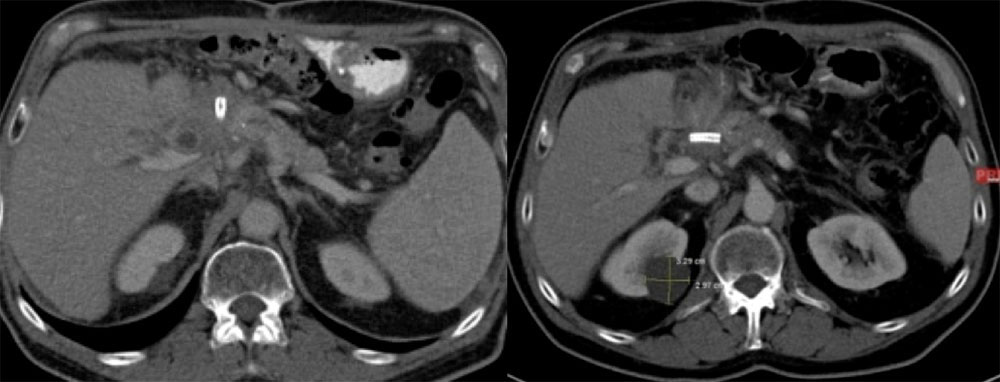

Case 13  Abdominal images on a 60 year old woman show small bowel obstruction and:

|

Case 13  Abdominal images on a 60 year old woman show small bowel obstruction and:

|

Retained Capsule Endoscopy

|

Retained Capsule Endoscopy

|